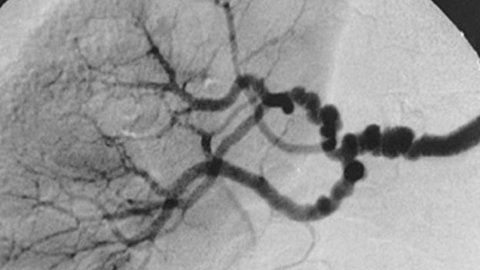

A client with a serious circulatory problem—a failed femoral-popliteal bypass, or “fem-pop” surgery—wants a massage while he’s waiting for his next procedure. There’s no data on massage and failed fem-pops at all. What can this massage therapist do? In this episode, we look at fem-pop surgeries and the reasons why a person might need it. Then, we take apart some of the variables that go into making decisions about massage therapy for this client. It’s a critical-thinking exercise with immediate repercussions for this client and his health and comfort.